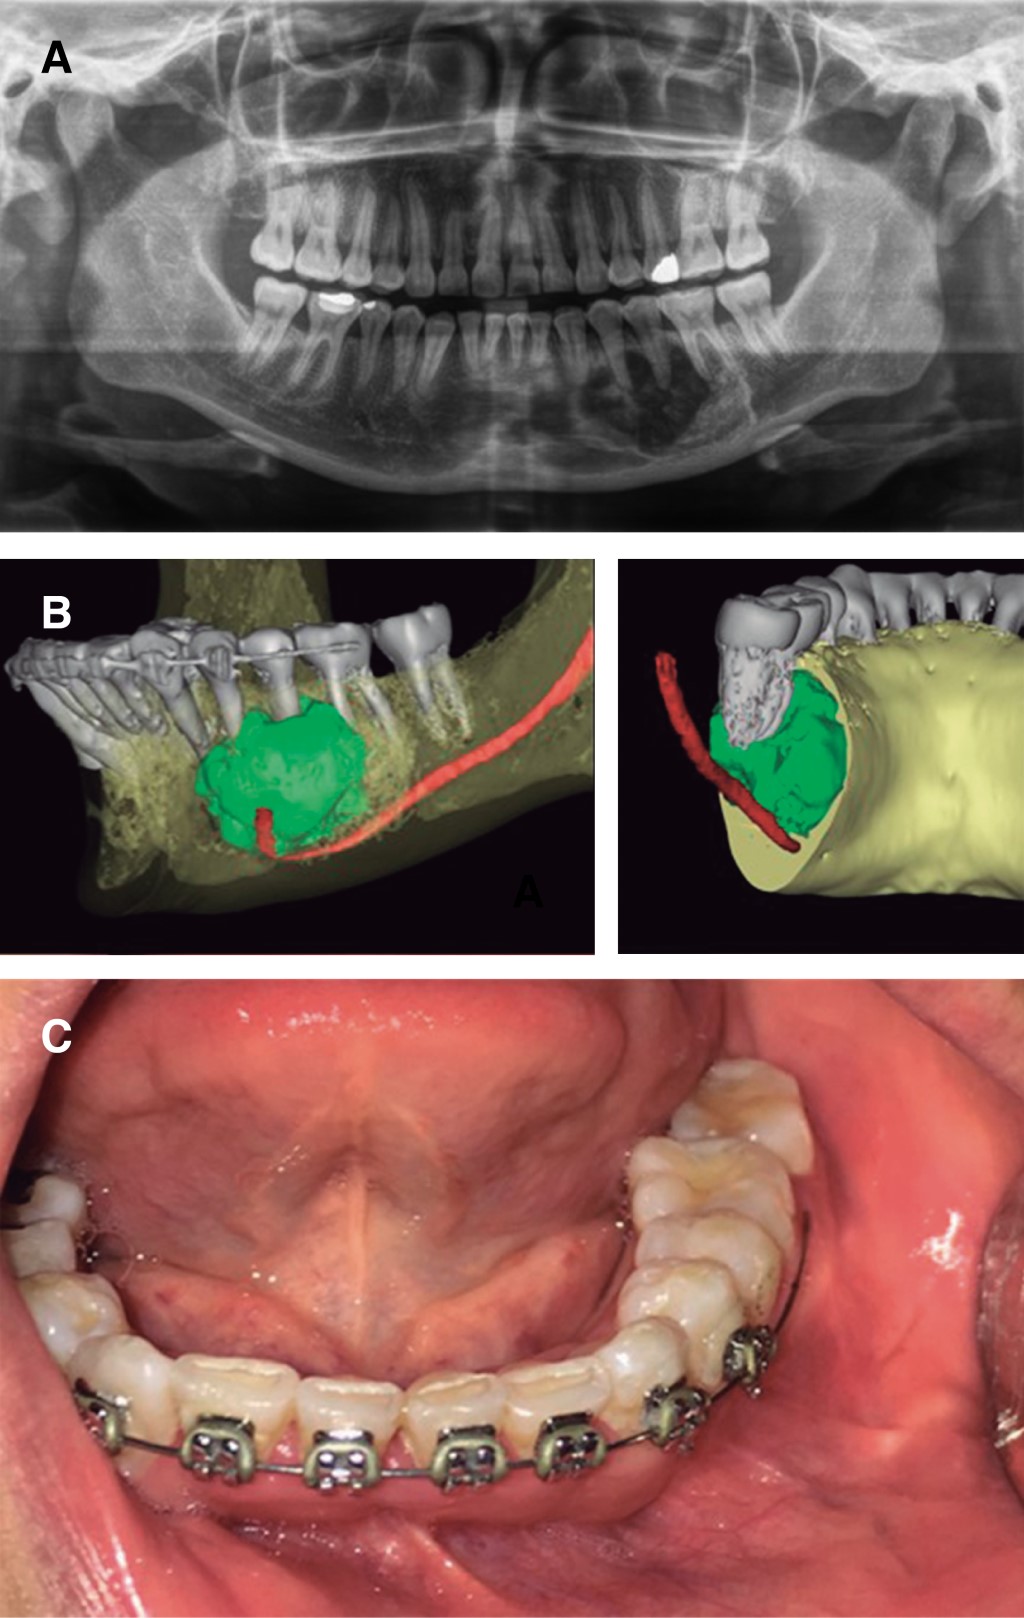

Las lesiones híbridas se consideran una patología rara que presenta elementos de diferentes entidades, cada una de las cuales tiene una categoría tumoral. En la actualidad hay menos de diez casos notificados de lesiones híbridas que muestran la asociación de una lesión central de células gigantes y un fibroma osificante. Dado que un protocolo de tratamiento para este tipo de patologías no está bien establecido en la literatura, presentamos un caso de manejo integral, incluyendo la rehabilitación, basado en la revisión de la literatura. Se trata de una paciente de 31 años con un diagnóstico inicial de lesión central de células gigantes en el cuerpo mandibular izquierdo, que fue tratada con triamcinolona intralesional, sin encontrar respuesta tras seis semanas de tratamiento, por lo que decidimos realizar una resección en bloque de la lesión y la reconstrucción simultánea con un injerto libre de cresta ilíaca anterior, obteniendo un resultado histopatológico definitivo de lesión híbrida (lesión central de células gigantes más fibroma osificante), posteriormente se realizó una rehabilitación protésica implantosoportada. En los casos de lesiones híbridas, consideramos que el manejo quirúrgico es adecuado, dado el comportamiento particular de dicha entidad que no responde adecuadamente al manejo farmacológico, recomendamos evitar el uso de medicamentos antirresortivos ya que perjudicaría el resultado de un tratamiento quirúrgico y reconstructivo posterior.

Figura 1